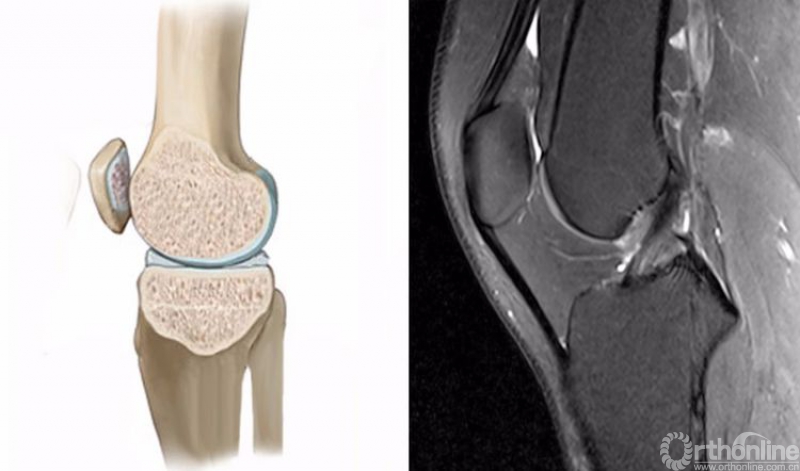

正常的膝关节进行MRI扫描时,不管任何一个序列,其骨髓信号一般T1WI呈均匀一致的灰色,T2WI及STIR呈均匀一致的黑色。

2.膝关节矢状位的正常MRI图像